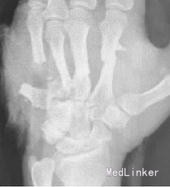

入院诊断左手损伤,左第2~5掌骨开放性粉碎性骨折,左第2~5指伸肌撕脱损伤,左手背软组织挫裂伤伴缺损,左中、小指指深屈肌腱断裂,左环指指深屈肌腱撕脱损伤,左手骨间肌、蚓状肌断裂、挫裂伤,左手指掌侧总神经、指背侧总神经及指神经断裂,左手指掌指总动静脉、掌浅弓、掌深弓断裂,左手掌软组织挫裂伤,左大小鱼际肌部分断裂,左桡骨下段横形骨折,左肘部软组织损伤。入院后给予急诊清创固定1周后左小指、环指缺血坏死,再次手术行左环、小指切除,左第5掌骨切除、左第4掌骨残端修整、左桡骨下端切开复位固定术,左第2、3掌骨骨折端术后5个月无愈合迹象。术后X线片提示:骨折断端存在间隙,骨痂很少或无,断端分离,髓腔封闭,骨质疏松,无骨小梁形成,符合骨折不愈合诊断。